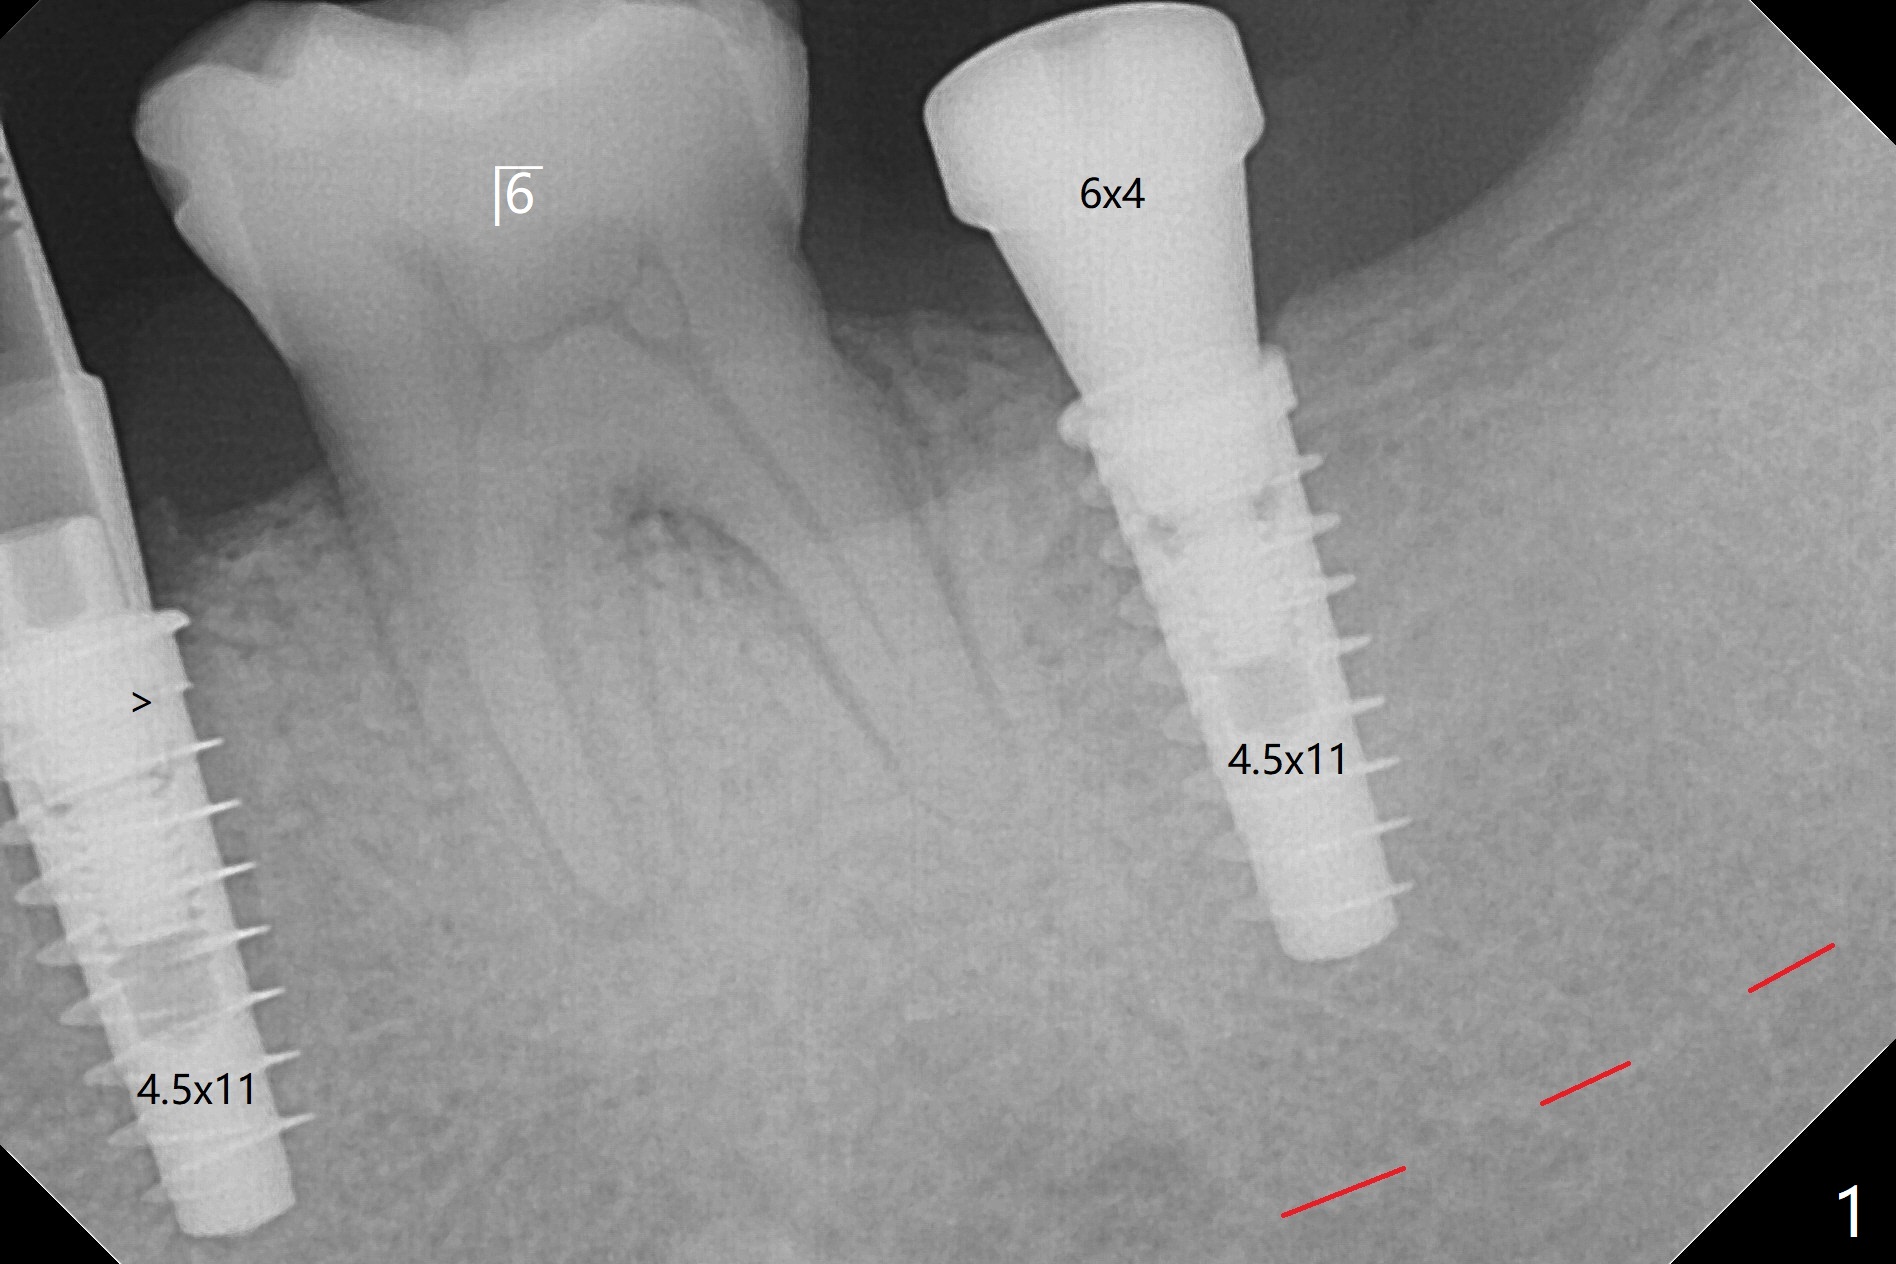

为了预防钻头遇到舌侧骨板而往颊侧偏移,有意不拔除第二前磨牙牙根。但是2.2毫米钻头钻洞很吃力,最后不得不拔除牙根,阻力骤然减少,顺利完成植入,而且颊侧间隙还够(图一,二),填入骨粉后远中螺纹间空间消失(图三箭头)。今后最后一个钻头完成钻洞后留在原位,周围放置适当量的骨粉,然后取出钻头,植入植体,这样空间可以比较全面充填。即刻种植没有颊侧偏移可能是因为设计时植体没有过多接触舌侧骨板(图四L)。第二磨牙延期种植需要切开是因为颊侧角化牙龈不足。术后两个月,前磨牙植体顶端似乎被牙槽嵴覆盖了(图五 *)。术后五个月,旋转7愈合基台,下面植体疼痛,可能与植体螺纹断裂有关(图六:>),5取模。